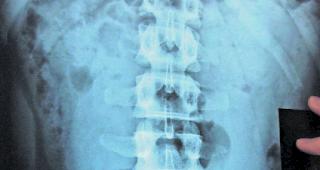

Beweismittel. Die Röntgenaufnahme zeigt mehrere der Fingerlinge im Darm eines Bodypackers.

Drogenschmuggel | Im Oberwallis wird jeden...

Drogenkuriere mit vollem Magen

Walliser Bote | Oberwallis. Was viele aus Hollywoodverfilmungen über kolumbianische Drogenkartelle kennen, gehört [...]